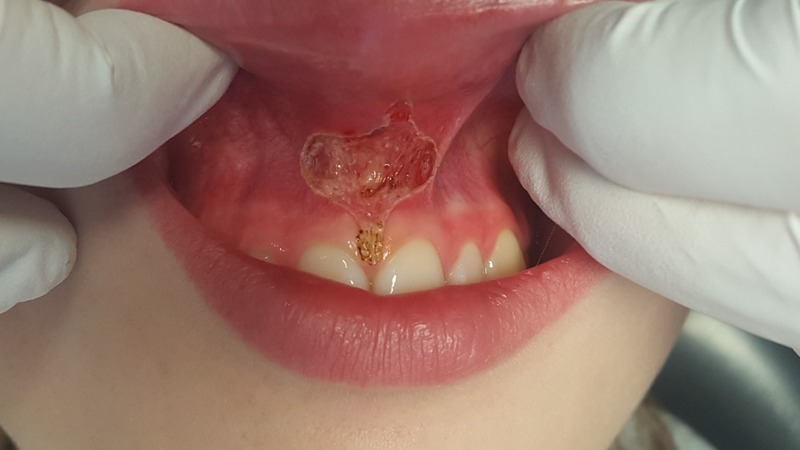

• Klinické případy použití laseru + dokumentace zákroků a následného hojení.

• Klinické případy s dokumentací.